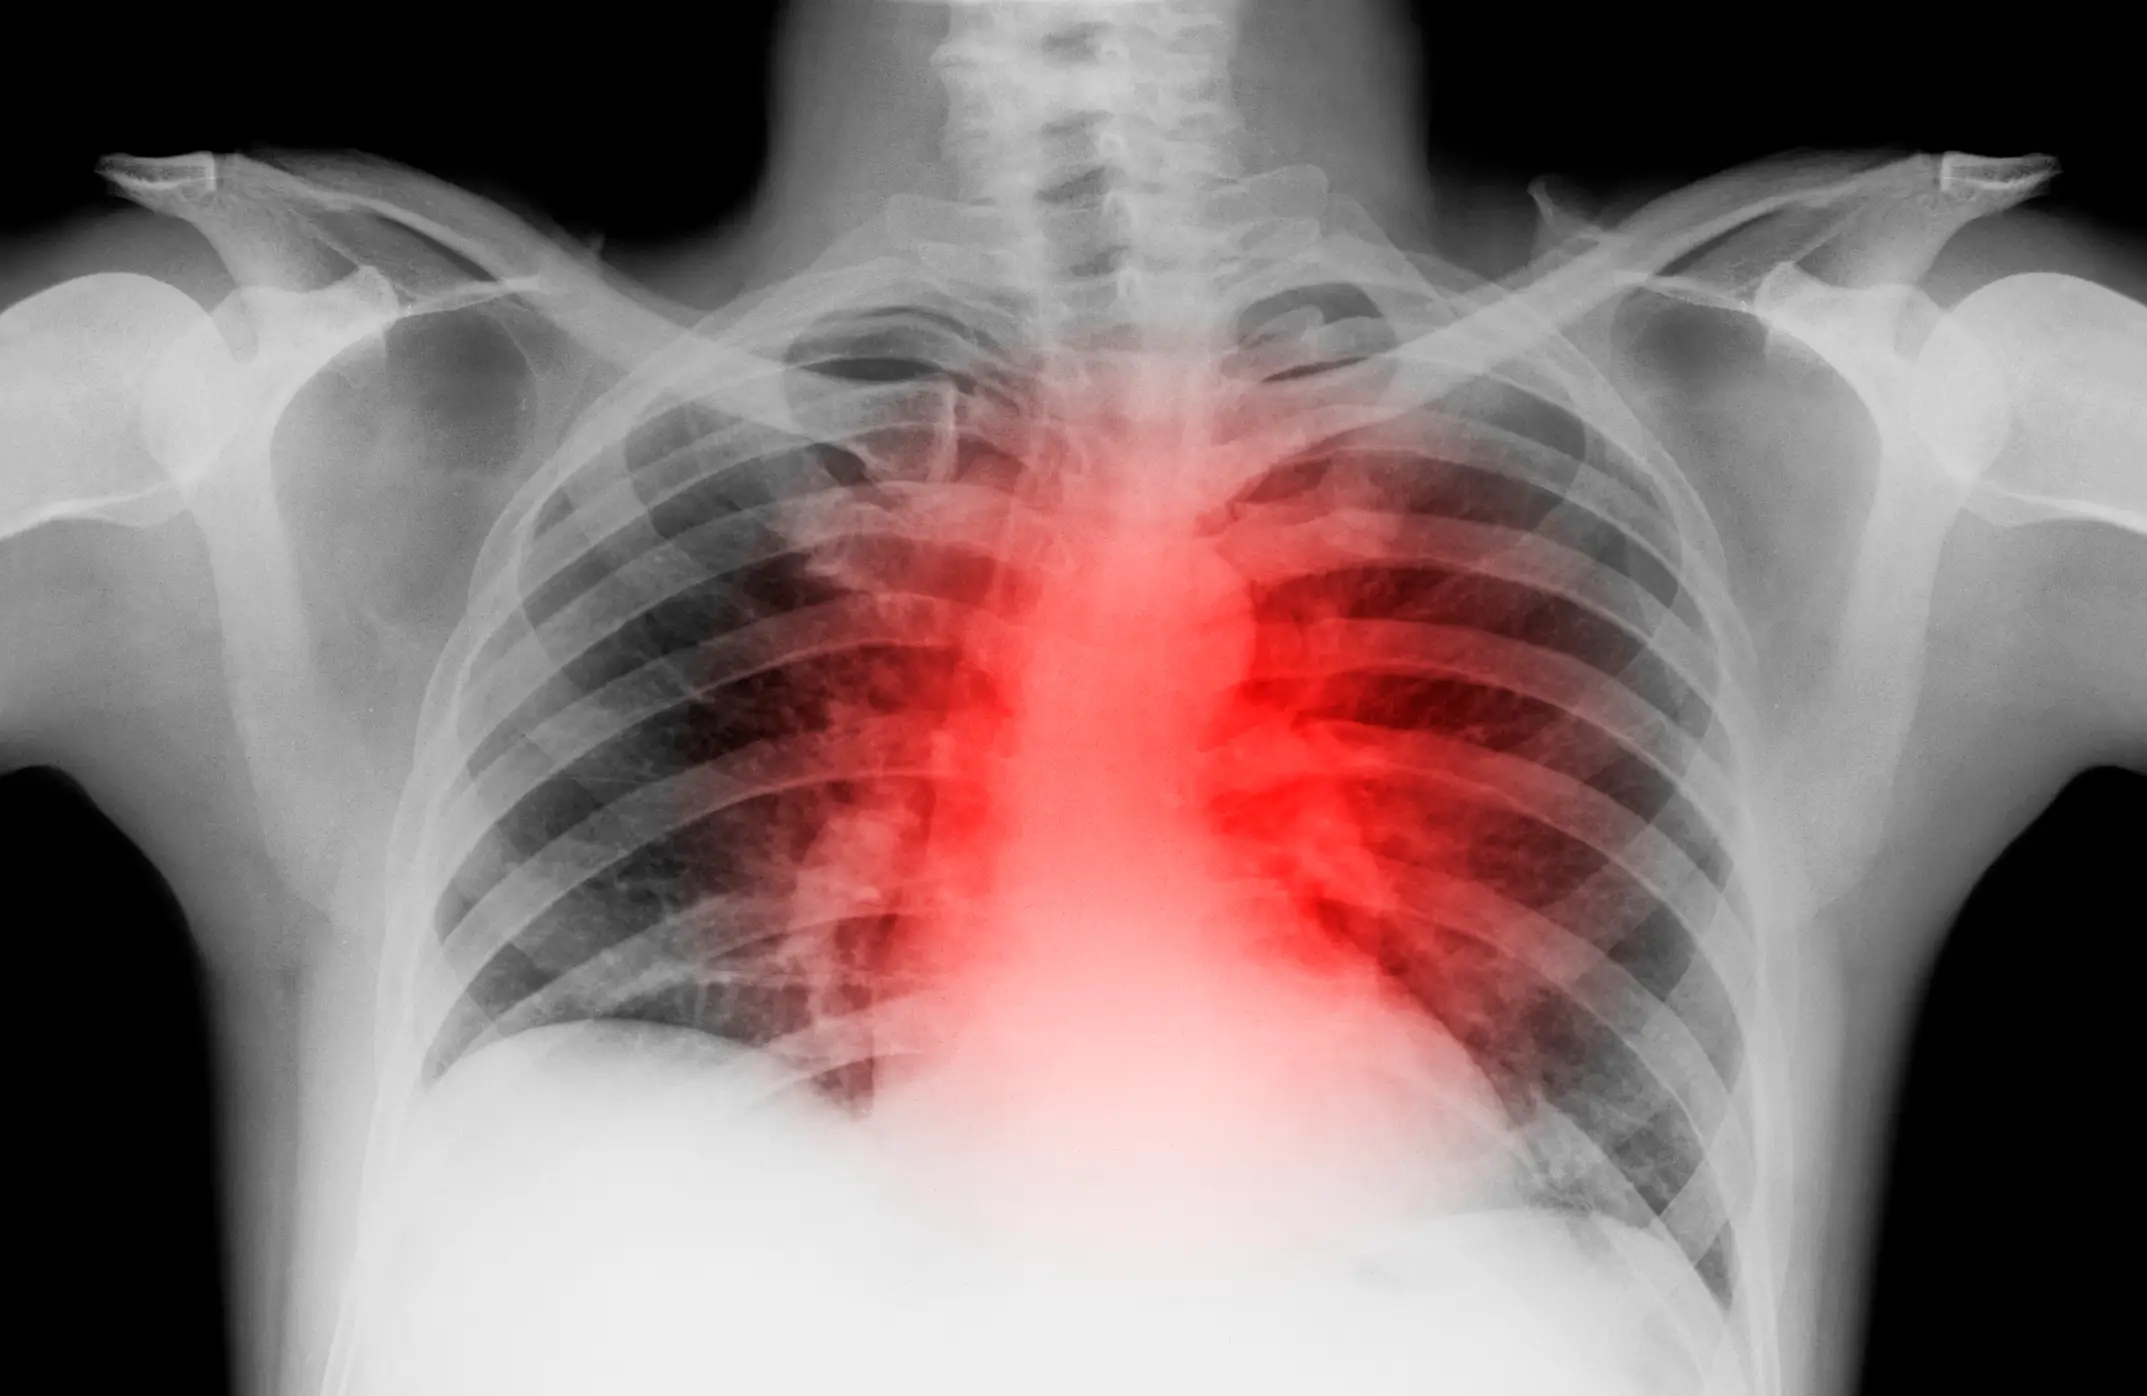

In fact, it can possibly indicate poor cardiovascular health - in other words, issues related to the heart and blood vessels.

However, many studies have noted the presence of the unusual mark in those with cardiovascular issues, such as heart disease and atrial fibrillation, a condition which causes an irregular heartbeat.